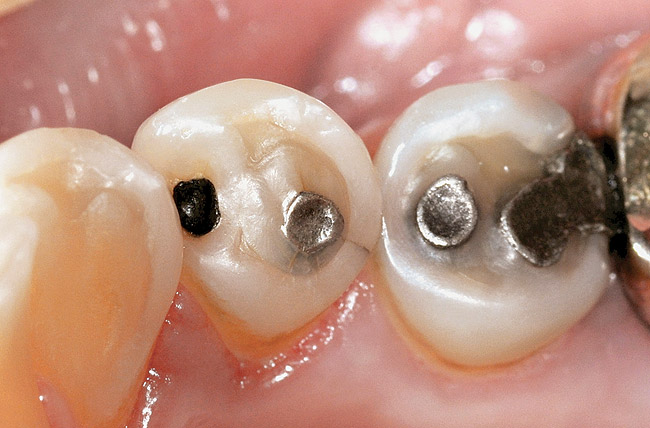

Figure  2  Loss of tooth surface surrounding amalgam and appearance of the restoration protruding from the tooth surface.

Figure 2

Characteristics of damage to tooth structures caused by acidity include wear on the occlusal surfaces of molars and a saucer shape on the cusps of molars (perimolysis).12 The erosion can vary from minor and subtle changes on the tooth surface, ie, loss of luster, a dull or matted look, to cupping on occlusal surfaces or incisal edges, which may extend to dentin. Usually, the erosive lesions demonstrate greater width than depth. When combined with abrasive forces or stresses, the tooth surface loss may occur at a faster rate (Figure 2, Figure 3, Figure 4 and Figure 5).